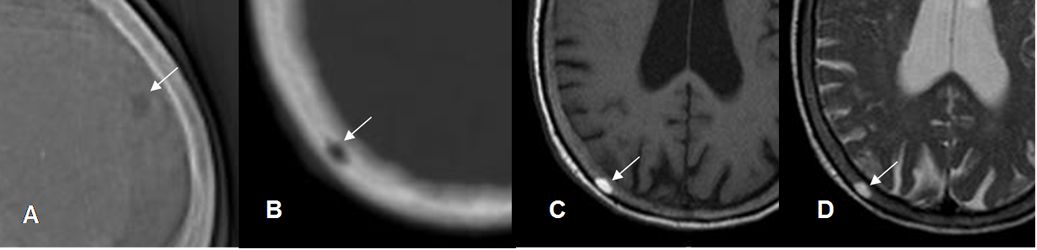

Fig 156. Hemangioma óseo.

A: Rx lateral y B: TAC axial. Lesión radiolúcida y de contornos definidos y no escleróticos.

C: RM axial en T1 y D: RM axial en T2. Esta lesión es hiperintensa en ambas secuencias y corresponde a un hemangioma.